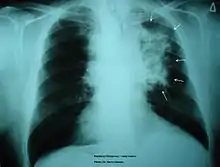

The morbidity of cigarette smoking is nearly 50% with 7 million first-hand smokers and 1.2 millions second hand smokers killed each year.[8] Regardless of active or passive smokers, macrophage accumulation is found in the lungs.[3][5] The diagnostic methods for smoke-related diseases include bronchoalveolar lavage which can also be used for examining smoker's macrophages in addition to augmented inflammatory cells in the alveolar lumen.[1]

The immune functions in smoker’s macrophages are compromised, so the airway pathogens are more likely to accumulate and cause infection.[17] Smoker’s macrophages have reduced expression of HLA-DR antigens, causing immunosuppression.[18][19] In addition, nicotine impairs the phagocytosis of M. tuberculosis and also induces immunosuppression via the activation of alpha-7 nicotinic receptors.[4][17] Meanwhile, due to the impaired TLR2 and TLR4 signaling, macrophages fail to recognize pathogens, so there is a decrease in pathogen clearance.[17] Therefore, smokers are prone to acute respiratory tract infection and community acquired pneumonia.[20]

Chronic Obstructive Pulmonary Disease

Smoking is found to be the most important causative factor leading to COPD.[23] Because of the altered inflammatory response of the macrophages, smoking induces inflammation across the entire airway, which in turns obstructs the airflow. Symptoms of COPD include persistent coughing, wheezing, chest infections and breathlessness. Treatments for COPD usually focus on the source of the problem, which is smoking, thus the general treatment is going through smoking rehabilitation which including nicotine replacement therapy, mental therapy for advice, and support to quit smoking. In certain urgent cases, direct constriction also occurs, in which bronchodilators allow the airway to dilate.